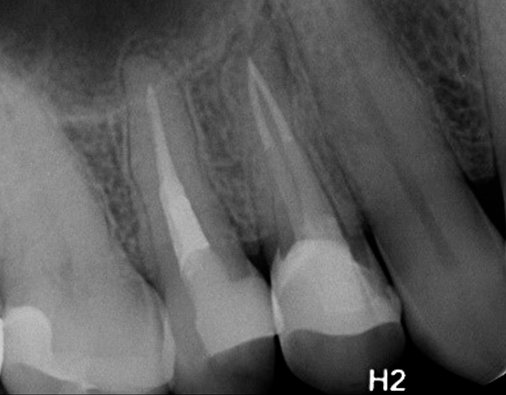

Den perfekte rodfyldning... eller næsten.

Med denne teknik laves der et apikalt plug med en masterpoint der varmes ned til 4-6 mm. Derefter fyldes rodkanalen med flydende guttaperka med backfill teknik.

Billeder venligst udlånt af tandlæge Thomas Hedegaard.